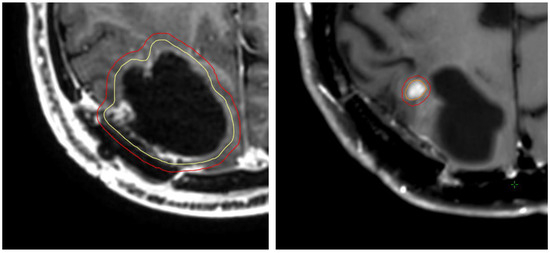

Assessing Impact of Data Quality in Early Post-Operative Glioblastoma Segmentation

Quantification of the residual tumor from early post-operative magnetic resonance imaging (MRI) is essential in follow-up and treatment planning for glioblastoma patients. Residual tumor segmentation from early post-operative MRI is particularly challenging compared to the closely related task of pre-operative segmentation, as the [...] Read more.

Quantification of the residual tumor from early post-operative magnetic resonance imaging (MRI) is essential in follow-up and treatment planning for glioblastoma patients. Residual tumor segmentation from early post-operative MRI is particularly challenging compared to the closely related task of pre-operative segmentation, as the tumor lesions are small, fragmented, and easily confounded with noise in the resection cavity. Recently, several studies successfully trained deep learning models for early post-operative segmentation, yet with subpar performances compared to the analogous task pre-operatively. In this study, the impact of image and annotation quality on model training and performance in early post-operative glioblastoma segmentation was assessed. A dataset consisting of early post-operative MRI scans from 423 patients and two hospitals in Norway and Sweden was assembled, for which image and annotation qualities were evaluated by expert neurosurgeons. The Attention U-Net architecture was trained with five-fold cross-validation on different quality-based subsets of the dataset in order to evaluate the impact of training data quality on model performance. Including low-quality images in the training set did not deteriorate performance on high-quality images. However, models trained on exclusively high-quality images did not generalize to low-quality images. Models trained on exclusively high-quality annotations reached the same performance level as the models trained on the entire dataset, using only two-thirds of the dataset. Both image and annotation quality had a significant impact on model performance. In dataset curation, images should ideally be representative of the quality variations in the real-world clinical scenario, and efforts should be made to ensure exact ground truth annotations of high quality. Full article